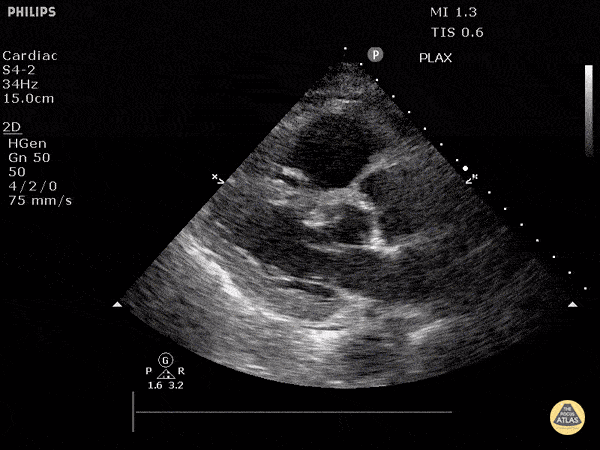

Right Ventricular Dysfunction - Acute Cor Pulmonale (Parasternal Long-Axis View)